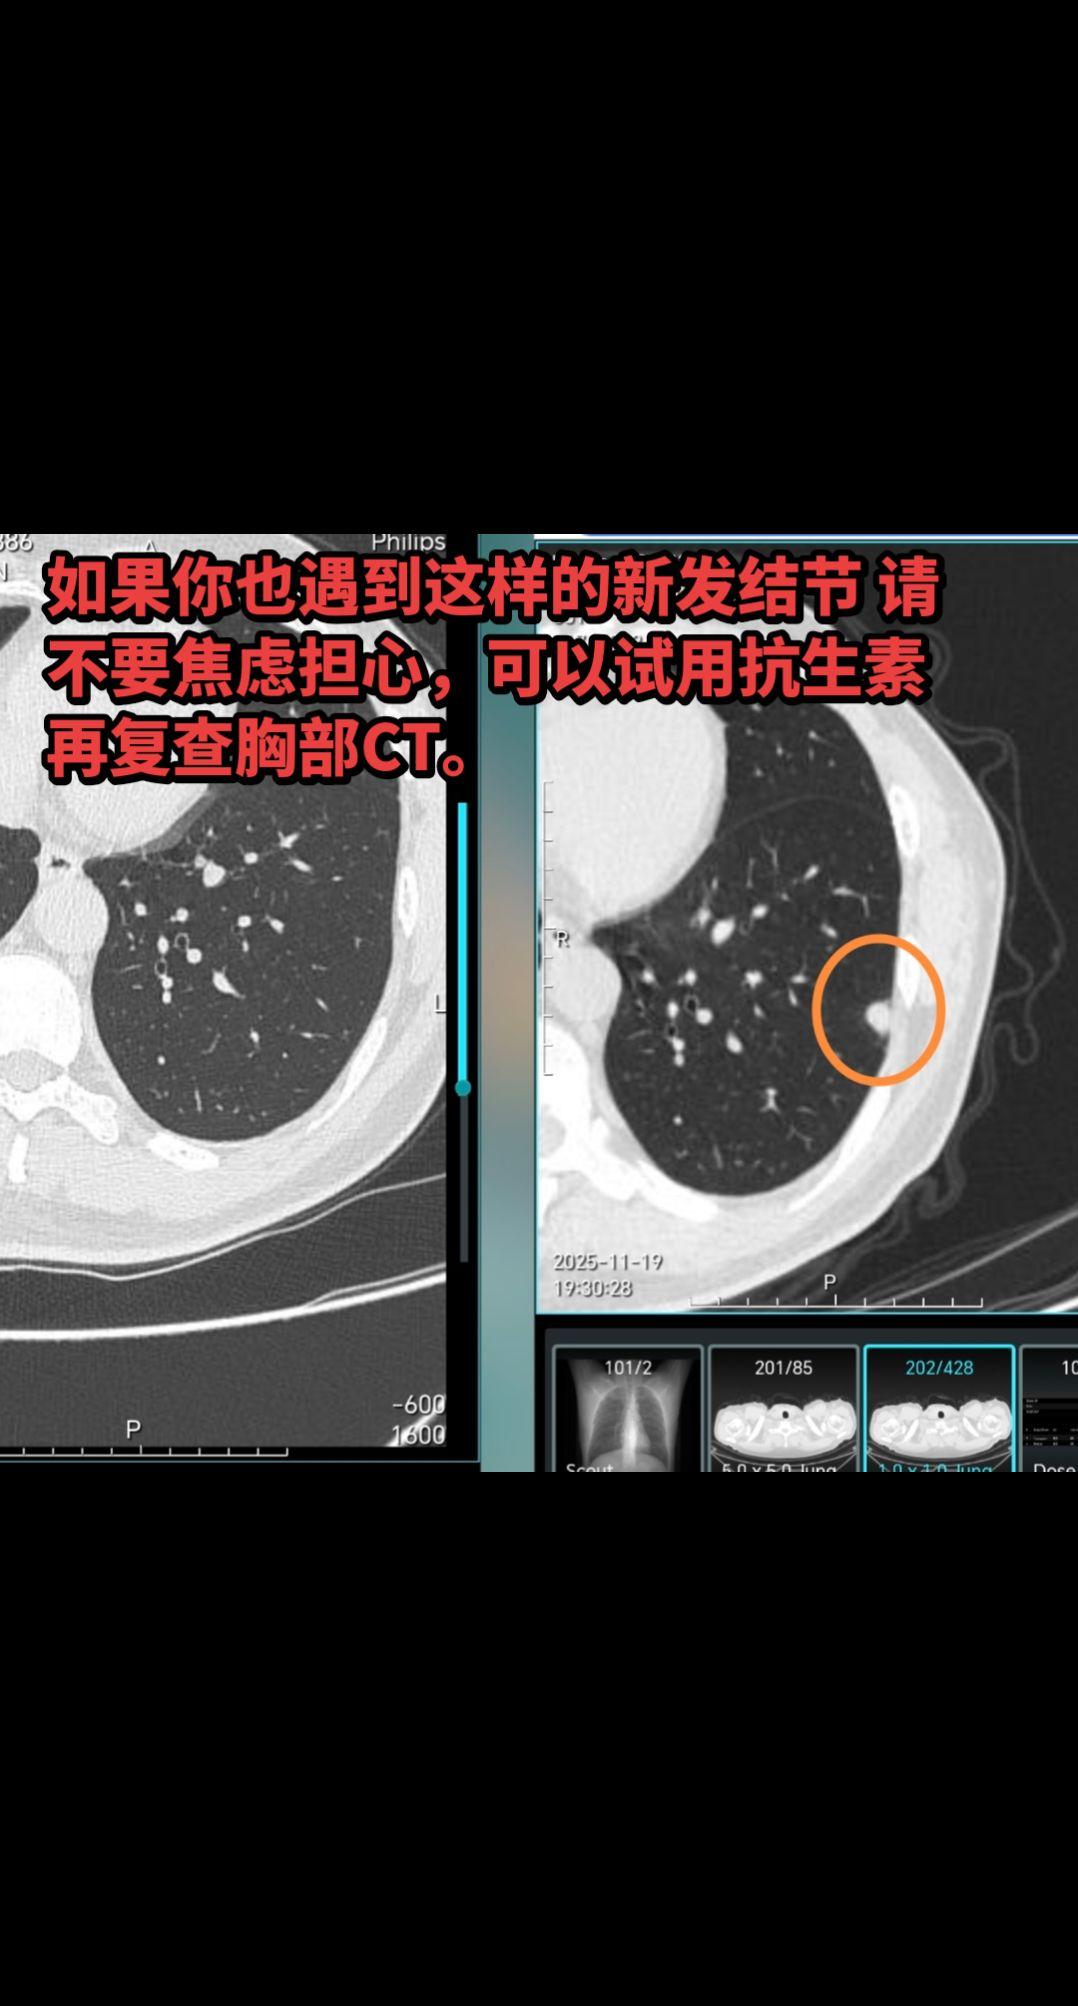

这类结节多考虑炎症,无须担心!该患者 2024.11 曾因其他结节复查胸部 CT,今年例行年度复查发现新增了两个结节,一个是实性结节,另一个是磨玻璃结节。像此类在半年到一年新出现的实性结节或磨玻璃结节一般考虑是炎性结节。因为肿瘤性的结节不会在短期内突然出现,只有炎性结节才会在短期内出现。如果你也遇到这样的新发结节 请不要焦虑担心,可以试用抗生素 再复查胸部CT。